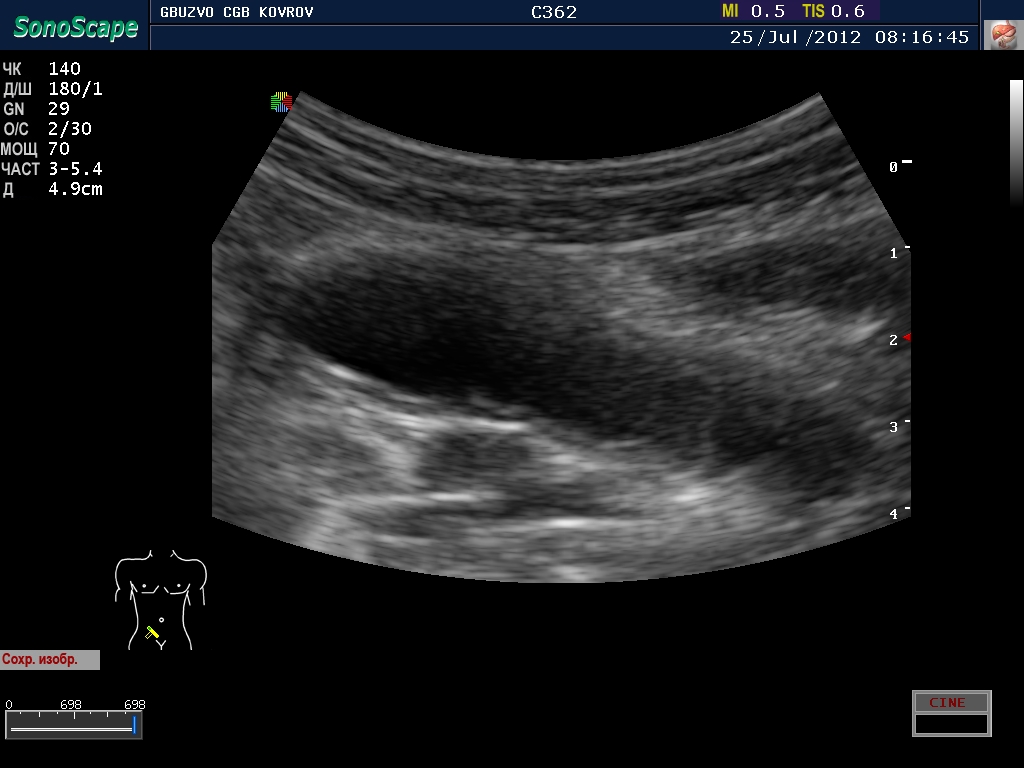

Пациент с жалобами на боли в животе...

jul252012081644.jpg

jul252012081644.jpg [ 202.73 KiB | Просмотров: 23988 ]

Что это такое? Кишка?

ну, скажем так, часть кишечника :D

поподробнее? :shock: бодимаркер находится в правой подвсздошной области, я бы подумал про аппендикс 8-)